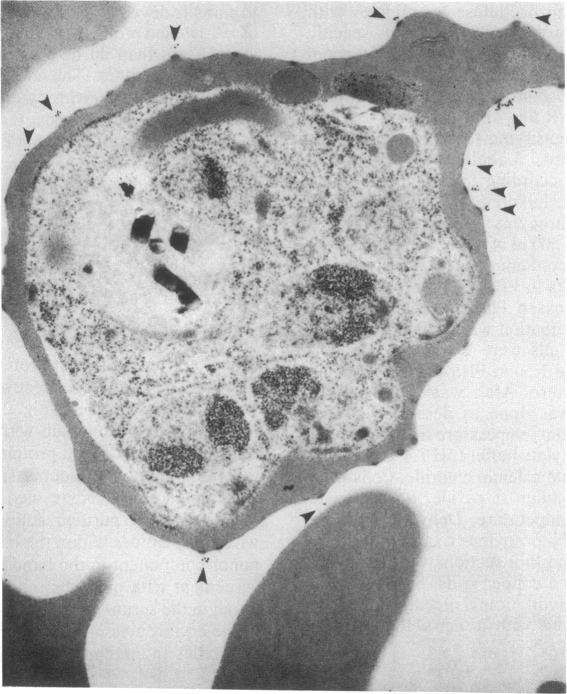

Erythrocytes infected with a knobby variant of Plasmodium falciparum selectively bind IgG autoantibodies in normal human serum. Quantification of membrane-bound IgG, by use of 125I-labeled protein A, revealed that erythrocytes infected with the knobby variant bound 30 times more protein A than did noninfected erythrocytes; infection with a knobless variant resulted in less than a 2-fold difference compared with noninfected erythrocytes. IgG binding to knobby erythrocytes appeared to be related to parasite development, since binding of 125I-labeled protein A to cells bearing young trophozoites (less than 20 hr after parasite invasion) was similar to binding to uninfected erythrocytes. By immunoelectron microscopy, the membrane-bound IgG on erythrocytes infected with the knobby variant was found to be preferentially associated with the protuberances (knobs) of the plasma membrane. The removal of aged or senescent erythrocytes from the peripheral circulation is reported to involve the binding of specific antibodies to an antigen (senescent antigen) related to the major erythrocyte membrane protein band 3. Since affinity-purified autoantibodies against band 3 specifically bound to the plasma membrane of erythrocytes infected with the knobby variant of P. falciparum, it is clear that the malaria parasite induces expression of senescent antigen.